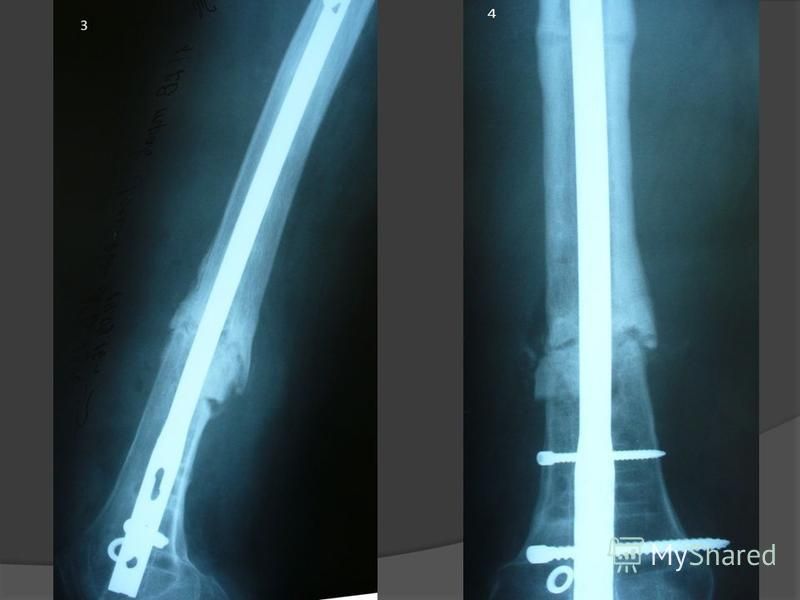

Классификация переломов диафиза бедренной кости: Иллюстрации и информация